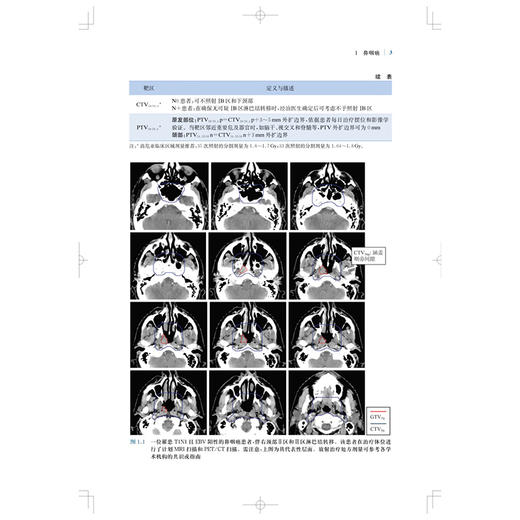

肿瘤放射治疗靶区勾画与射野设置是疗效的基石,精准的靶区范围的确定和勾画可确保肿瘤患者的放疗效果。全书结合大量影像图片,按章分别详细介绍了各种常见病变的具有临床依据的精确的CTV勾画和指南,包括鼻咽癌、甲状腺癌、早期乳腺癌、肺癌、直肠癌、前列腺腺癌、膀胱癌等;并对相关的淋巴引流区解剖进行了勾画,且逐层显示并说明注意事项。本书内容实用,可为放疗医师对常见肿瘤进行适形放疗和调强放疗时的靶区勾画及放射野设置提供指导和参考。